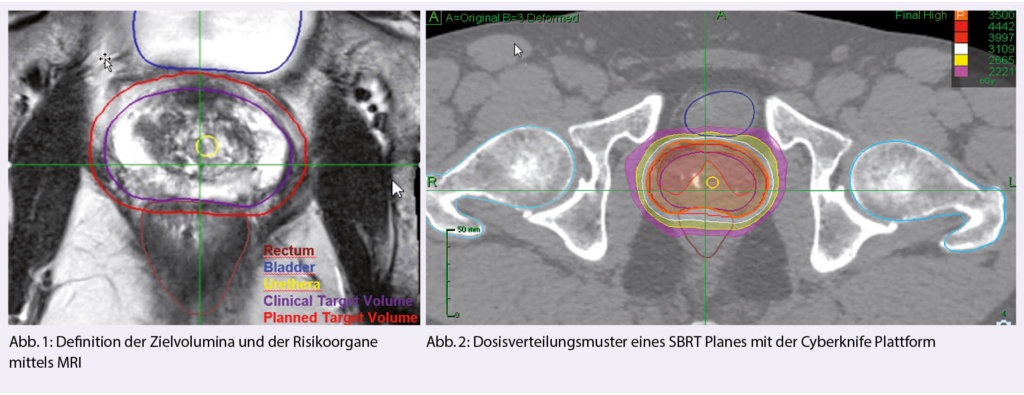

Die Definition des Zielvolumens ist für die Verwendung von SBRT entscheidend. Das Zielvolumen umfasst typischerweise die Prostata, mit oder ohne die proximalen Samenblasen und Bereiche mit extrakapsulärer Ausdehnung. Frühere Studien haben gezeigt, dass bei der Konturierung der Prostata eine signifikante Variation besteht, was die Notwendigkeit einer angemessenen Qualitätssicherung unterstreicht (25, 26). Zunehmend wird die Bildfusion von MRT-Sequenzen in die Praxis umgesetzt. Die Einbeziehung von MRT-Bildern reduziert die Variation zwischen den Beobachtern bei der Zielvolumendefinition im Vergleich zu reinen Computertomographie-Bildern.

In der Mehrheit der bisherigen veröffentlichten Studien wurde das CyberKnife zur Durchführung von SBRT verwendet, in neueren Serien wurde auch von Gantry-basierten Linacs mit ähnlichem Outcome berichtet (27, 28). Die grösste technische Herausforderung bei der Anwendung von SBRT auf die Prostata ist das Management der Beweglichkeit der Prostata während der Bestrahlung. Bildleitsysteme sind der Schlüssel zu einer sicheren Verabreichung von SBRT (Realtime Motion Tracking Systeme).